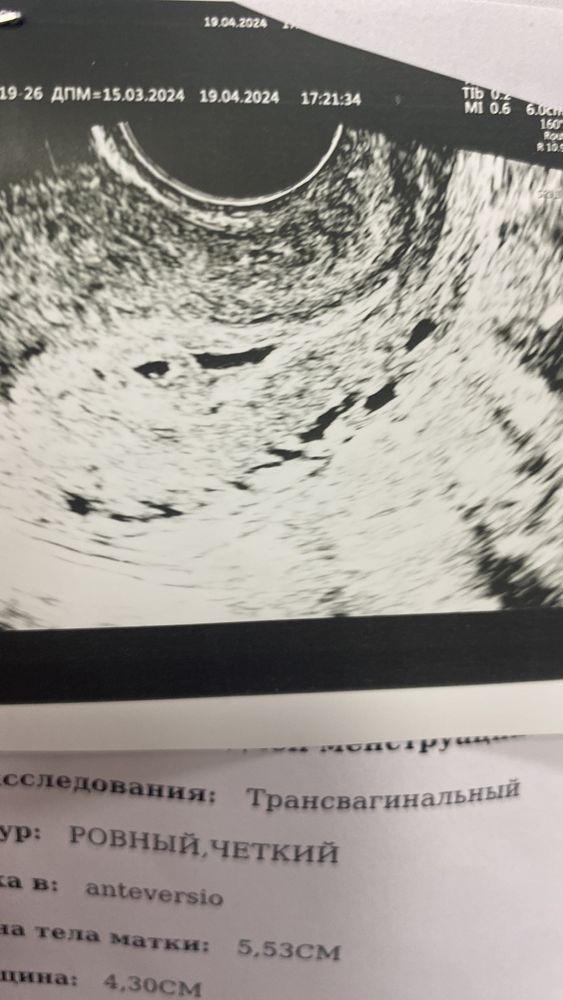

Девочки я сегодня пошла на узи примерно3-4неделья говорили гематома чут чуть .назначили дюфастон у к

Изображение